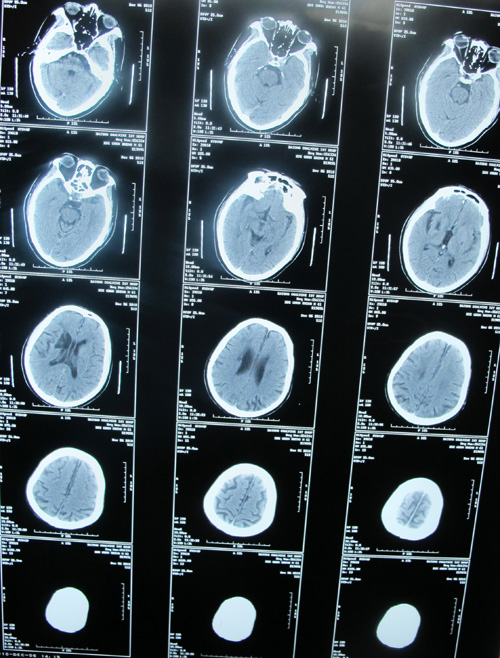

头颈CTA示:右侧颈内动脉近端闭塞,左侧颈总动脉远端及颈内动脉近端重度狭窄

脑梗塞(双侧基底节区)

陈旧性脑梗塞

该患者为急性起病,既往脑梗塞病史13年,心肌梗塞病史1年。右侧颈内动脉近端闭塞,左侧颈总动脉远端及颈内动脉近端重度狭窄,均达到手术指征。患者无明确手术禁忌症,故采取手术治疗,去除病变,改善症状并预防中风发作。